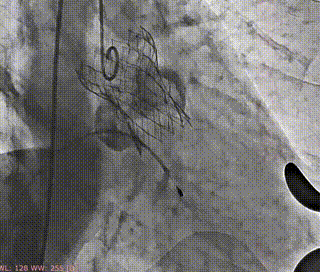

释放支撑臂

支撑臂释放后定位

瓣叶交界贴合释放瓣膜